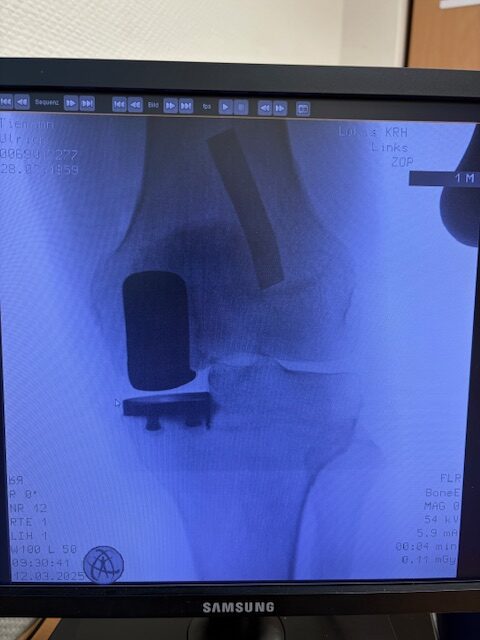

Ο ακτινολογικός έλεγχος (ακτινογραφίες/μαγνητική τομογραφία) ανέδειξε προχωρημένη οστεοαρθρίτιδα του έσω κονδύλου, με πλήρη διατήρηση του έξω διαμερίσματος και της επιγονατιδομηριαίας άρθρωσης. Με βάση αυτά τα ευρήματα, ο ασθενής ήταν ιδανικός υποψήφιος για μερική (μονοκονδυλική) αρθροπλαστική γόνατος.

Η επέμβαση πραγματοποιήθηκε με ελάχιστα επεμβατική προσπέλαση και τοποθέτηση πρόθεσης μόνο στον έσω μηροκνημιαίο διαμέρισμα του γόνατος.

Η ακριβής προσαρμογή του εμφυτεύματος επιβεβαιώθηκε διεγχειρητικά, εξασφαλίζοντας σταθερότητα και φυσική κίνηση της άρθρωσης.

Στον ασθενή τα εμφυτεύματα που χρησιμοποιήθηκαν είναι της εταιρείας Zimmer-Biomet Persona Μηριαίο μέγεθος 6, κνημιαίο μέγεθος Η και ενθέμα (inlay) Η li. 8mm.